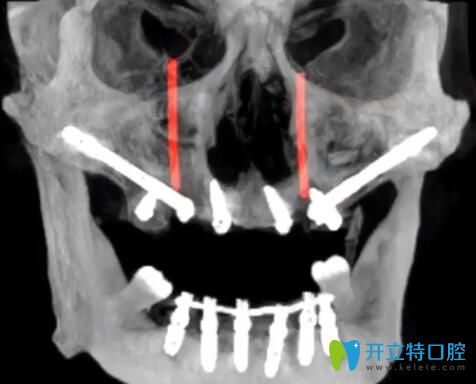

1、TPP穿翼板種植技術(shù)——牙槽骨條件差也能1天種好牙

大家知道種牙的必要條件就是有足量的牙槽骨,針對牙槽骨萎縮的人群,傳統(tǒng)的種植方法是骨增量,過程相對復(fù)雜,而且需要1年的恢復(fù)期。而黎強醫(yī)生的TPP穿翼板種植技術(shù),避開血管,把種植體種在牙齒與咽喉交界附近的十分堅硬的“翼狀板骨”上,將傳統(tǒng)種植1年才能解決的問題,在1天內(nèi)種好牙,且遠期效果好。

TPP穿翼板種植技術(shù)